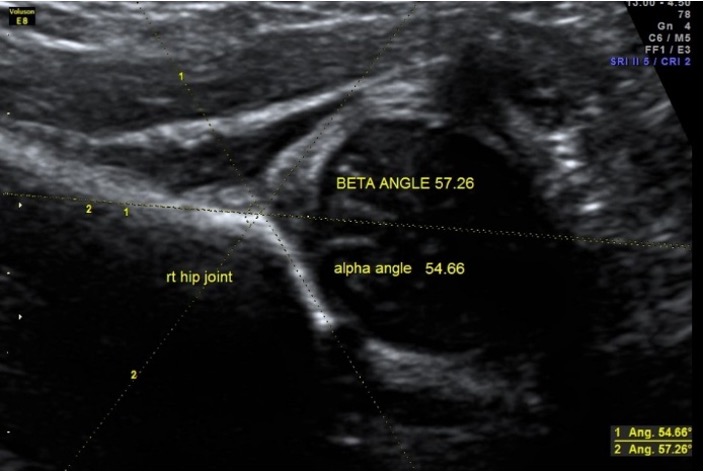

- The Graf method, which involves measuring the alpha angle (an indicator of acetabular development). A normal alpha angle is approximately 60 degrees, and deviations from this may suggest shallow sockets or DDH. In some cases, a misreading can be corrected by adjusting pressure during scanning, but persistently low values may confirm a diagnosis.

Figure 10: Ultrasound side view of the femoral head and acetabulum marked with angles.